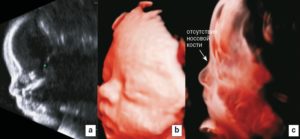

В качестве примера приведем несколько примеров: 1. Ниже на УЗИ мы видим нормальную носовую кость. Можно различить 3 четкие линии.

2. Гипоплазия носовой кости. УЗИ сделано на 12 неделе беременности. Длина — 1,4 мм (ниже границы нормы).

Размеры носовых костей плода зависят от срока беременности. Так, например, на 12–13 неделе беременности длина носовой кости всего лишь 3,0 мм. На 20–21 неделе она увеличивается до 5, 5 — 5,7 мм, а к 35 неделе беременности достигает 9,0 мм.